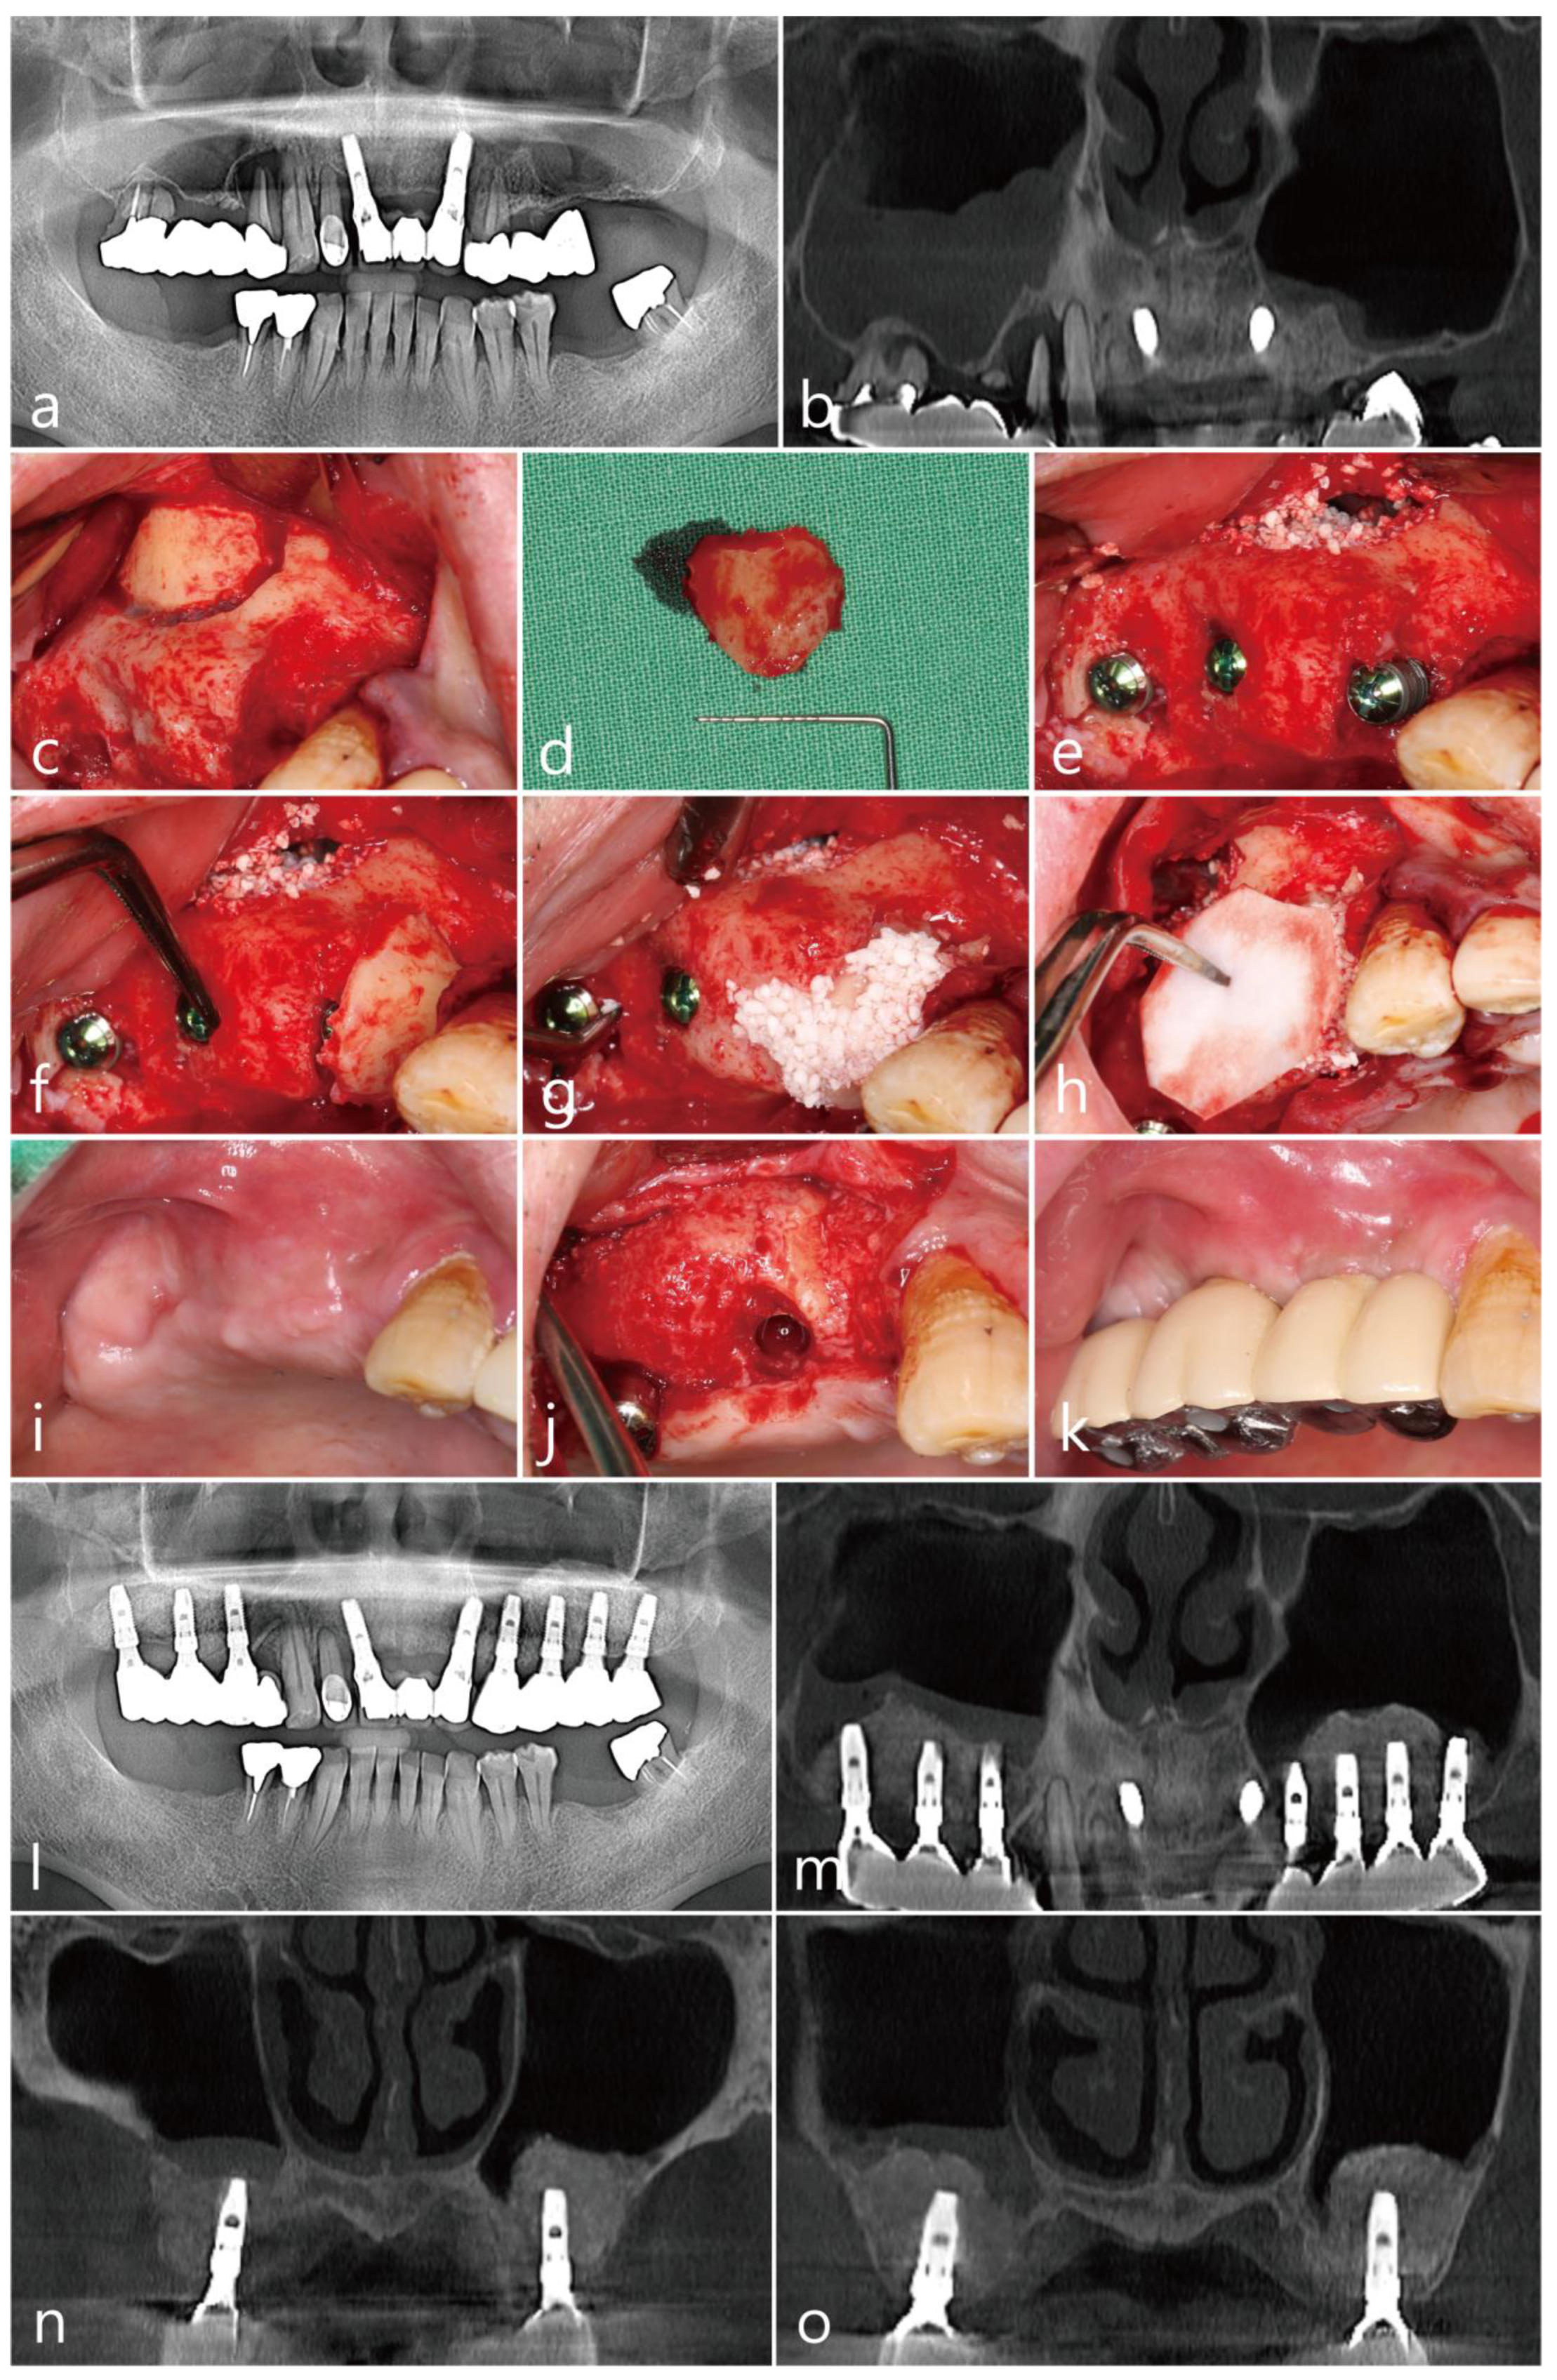

The patient was a 72 year old nonsmoking male (Table 1). An old prosthesis in the maxillary right posterior area was severely mobile, and the patient experienced discomfort during mastication. The patient requested implant-supported restoration after the removal of the old prosthesis. The preoperative panoramic radiograph showed severe bone resorption around teeth #14 and #17. A panoramic image of the CBCT before the surgery showed bony defects around the teeth and severe sinus mucosal thickening (Figure 4a,b).

Tooth extraction, MSA, and implant placement were planned simultaneously. Under local anesthesia with 2% lidocaine (containing 1:100,000 epinephrine), the mucoperiosteal flaps were reflected after extractions of the #14 and #17 teeth in the right maxillary posterior region. The lateral sinus window site was prepared using a #6 round bur (Ø1.6 mm; Azdent, Zhengzhou, Henan Province, China) (Figure 4c). The lateral bony window was obtained (Figure 4d). The sinus membrane was detached and elevated using a sinus elevation instrument (Genoss Co., Ltd., Suwon, Republic of Korea) without perforation. Three implants (Implantium, Dentium Co., Ltd., Suwon, Republic of Korea) were placed after MSA using an Osteon III (particle size 0.5–1.0 mm; Genoss Co., Ltd., Suwon, Republic of Korea) (Table 1). A severe bony defect was observed at the mesial site of the implant placed in the #15 site (Figure 4e). The obtained lateral sinus bony window was cautiously trimmed and placed in the mesial bony defect (Figure 4f). In the residual defect around the grafted lateral sinus bony window, a particulate bone graft substitute (Osteon III; particle size 0.2–0.5 mm; Genoss Co., Ltd., Suwon, Republic of Korea) was grafted (Figure 4g). The wound was covered with a resorbable collagen membrane (Genoss Co., Ltd., Suwon, Republic of Korea) (Figure 4h) and closed with 5-0 nylon. Antibiotics (ciprofloxacin; 500 mg; Ildong Pharmaceutical Co., Ltd., Seoul, Republic of Korea) and a nonsteroidal anti-inflammatory drug (Etodol; 200 mg; Yuhan Co., Ltd., Seoul, Republic of Korea) were prescribed for two weeks. No complications occurred during the healing, and the wound was not exposed (Figure 4i). The uncovering was performed six months after the surgery. The mesial bony defect around implant #15 was completely resolved, and the grafted lateral sinus bony window was well incorporated with the surrounding native bone (Figure 4j). The final prosthesis was delivered two months after the uncovering procedure (Figure 4k).

On the panoramic radiograph after the prosthesis delivery, the mesial bony defect of the #15 implant was filled with the grafted lateral sinus bony window and particulate bone graft (Figure 4l). The panoramic image of the CBCT scan showed a reduced sinus mucosal thickening and the incorporation of the grafted lateral sinus bony window with the surrounding native bone (Figure 4m). The coronal CBCT scans showed PSAAs on both sides. The diameter of the PSAA was 1.1 mm, and the vertical position from the floor of the right maxillary sinus was 19.9 mm (Table 1). On the coronal image of the CBCT at the #15 implant, the mesial bony defect was well resolved (Figure 4n). The coronal CBCT scan at the #16 implant (Figure 4o) showed reduced sinus mucosal thickening compared to the preoperative CBCT scan (Figure 4b).

Figure 4. Case 4: (a) preoperative panoramic radiograph; (b) panoramic image of the preoperative CBCT scan; (c) after flap reflection, the lateral bony window was prepared; (d) obtained lateral bony window; (e) implants were placed after the maxillary sinus augmentation; (f) the lateral bony window was cautiously trimmed and placed on the mesial bony defect; (g) additionally, particulate bone graft was used to fill the gap; (h) a resorbable collagen membrane was placed on the grafted site; (i) a clinical view at six months after surgery; (j) the grafted lateral bony window was well integrated with the surrounding native bone; (k) clinical view after prosthesis delivery; (l) panoramic radiograph at six months after prosthesis delivery; (m) panoramic image of the CBCT at six months after prosthesis delivery; (n) coronal image of the CBCT scan showing posterior superior alveolar arteries on both sides; (o) coronal image of the CBCT scan showing reduced mucosal thickening on the right maxillary sinus.